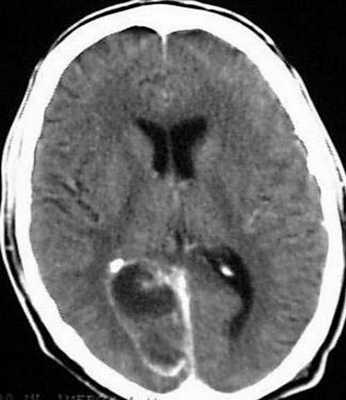

Для того чтобы провести точную диагностику места расположения абсцесса мозга и мозжечка, проводят компьютерную и магнитно-резонансную томографию головного мозга. При проведении компьютерной томографии выявляется тонкая, гладкая стенка абсцесса, которая имеет правильные контуры. Магнитно-резонансная томография позволяет также определить капсулу абсцесса. Если нет возможности провести вышеперечисленные виды исследования, можно провести пневмоэнцефалографию или радиоизотопную сцинтиграфию головного мозга.